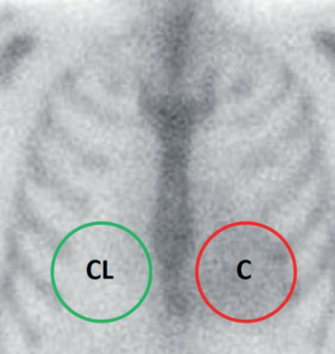

La interpretación de las imágenes con fosfonatos marcados requiere simplemente evaluar la presencia del radiotrazador en el área de proyección cardíaca y su comparación con la captación ósea fisiológica correspondiente al esternón y la parrilla costal, estableciendo una gradación visual o por métodos semicuantitativos. Perugini y col.(12) propusieron el uso de una sencilla escala visual para las imágenes de 3 horas, desde grado 0 a grado 3 según la intensidad de captación en el área cardíaca y su relación con la captación ósea (figura 1). Un estudio multicéntrico internacional que incluyó 1271 pacientes referidos por sospecha de AC demostró que un puntaje de Perugini ≥ 2 en ausencia de gammapatía monoclonal determinada en sangre y orina se asocia a una especificidad y valor predictivo positivo de 100% para AC-ATTR, con una sensibilidad del 72%(17). Sin embargo, hasta 20% de los pacientes tuvieron un pico de proteína monoclonal en las pruebas de laboratorio y la especificidad se ubicó en 91% en los pacientes en que no fue posible excluir AL por ese medio. Este hecho resalta la absoluta necesidad de contar con dosificación de cadenas livianas mediante estudios de inmunofijación al tiempo del estudio centellográfico. Bokhari y col.(15) desarrollaron un método de análisis semicuantitativo mediante un índice de captación corazón/tórax contralateral (C/CL) en las imágenes planares (figura 2) para distinguir la amiloidosis de tipo ATTR de la AL, con un valor de corte de 1,5 a los 60 minutos posinyección o de 1,3 a las 3 horas. El uso de esta metodología aplicando dichos valores de corte ha demostrado una sensibilidad y especificidad de 92% y 97% y de 88% y 86%, respectivamente(19).

Índice C/CL. Se mide la actividad (cuentas) en el área cardíaca (C) y se divide por la registrada en un área en espejo sobre el hemitórax contralateral (CL). Un valor ≥ 1,5 a una hora posinyección o ≥ 1,3 a las 3 horas sugiere ATTR.